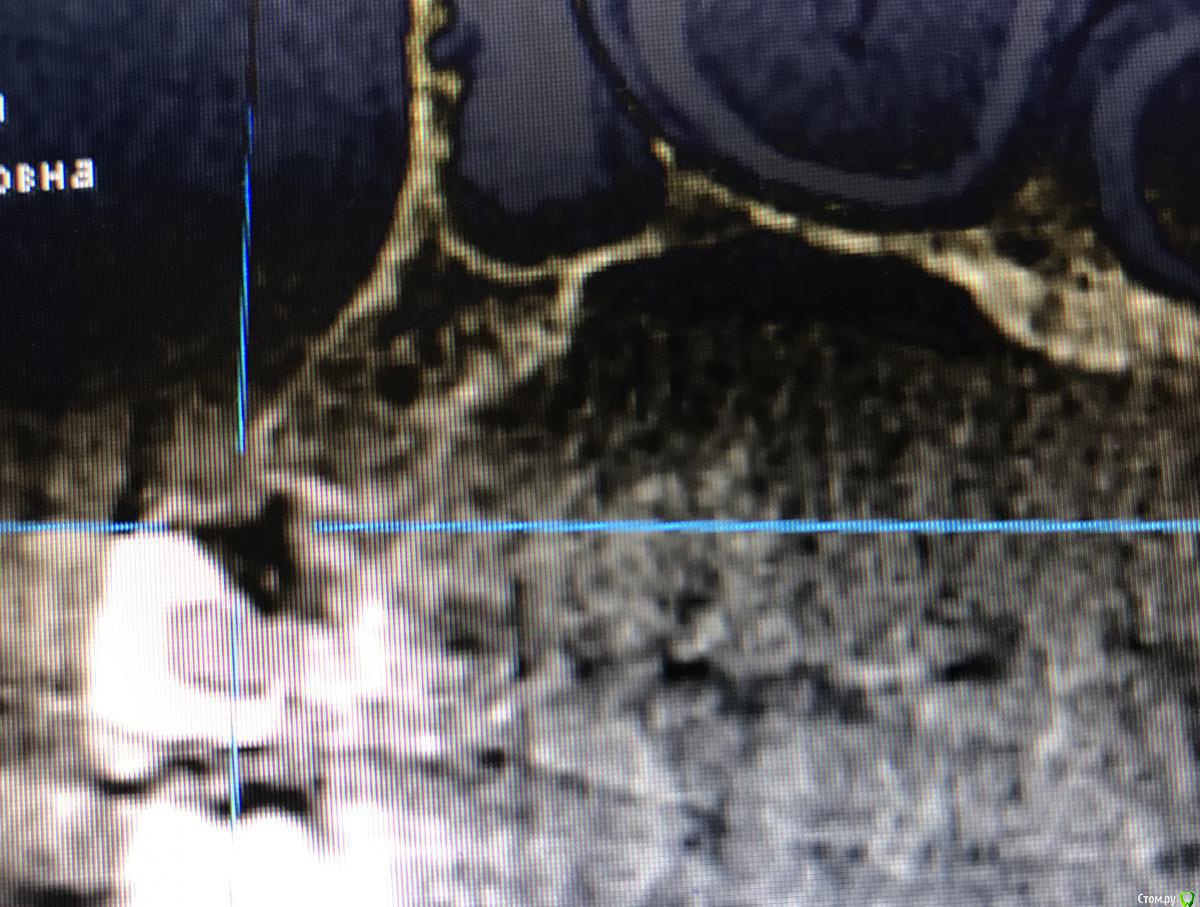

колесников Опубликовано 27 марта, 2018 Поделиться Опубликовано 27 марта, 2018 (изменено) Вот ещё случай (из интернета). Тут ситуация не однозначная,с одной стороны абатмент изначально из диоксида циркония,а с другой это похоже штрауман тл . завтра скину свой случай,у меня мис стоит стандартный абатмент и коронка с розовой десной. Суть примерно такая же. Вестибулярное положение платформы из-за угла положения импланта,лизис компактной пластинки и прогнозируемо рецессия. Видно,что закрывать массированно мягкими тканями не резон,будет шишка. Надо смещаться коронально,но придётся менять форму абатмента и коронки чтобы было где расположится прикреплённой слизистой. Так вот,на платформенном соединении это практически не возможно сделать ,угроза переточить стенку абатмента и получить перелом. Проще переустановить Имплант в другом положении. Но иногда это практически не возможно Изменено 27 марта, 2018 пользователем колесников Ссылка на комментарий